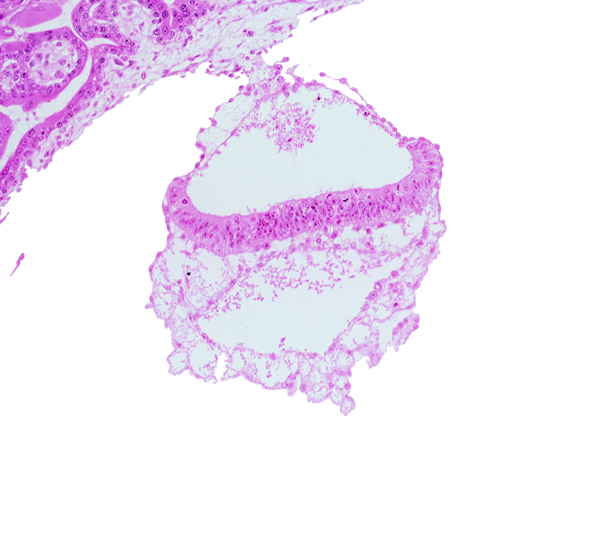

Carnegie Embryo #7802 | Location: 43-02-04

Keywords: amniotic cavity, cephalic end of notochordal process, epiblast, extra-embryonic endoderm, hemangiogenic tissue, hypoblast, mesothelium of umbilical vesicle, presumptive neural plate, two-layered amnion, umbilical vesicle cavity

Source: The Virtual Human Embryo.